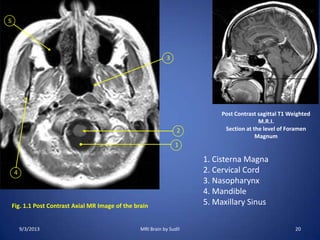

Fig. 1.4 Post Contrast Axial MR Image of the brain

Post Contrast sagittal T1 Wtd M.R.I.

Section at the level of Mid Brain

18. Aqueduct of Sylvius

19. Midbrain

20. Orbits

21. Posterior Cerebral Artery

22. Middle Cerebral Artery